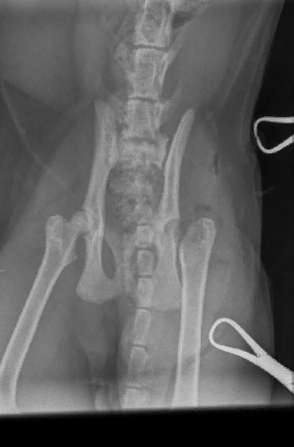

Однако в этот момент на руках у хозяйки пострадавшего четвероногого уже было заключение и рентгеновский снимок, на котором чёрным по белому написано, что у кота перелом.

Врач из ветклиники «Вет ZOO Доктор» — пишет, что у животного был выявлен «эпифизеолиз головки бедренной кости», что означает, что у животного присутствовала аномалия развитии. Однако на заключении, которое выдали женщинам после рентгена и проведённой операции, нет ни слова про «врождённую аномалию». В выписке из медицинской карты животного говорится, что у кота был диагностирован перелом головки бедренной кости и проведена операция по её удалению.